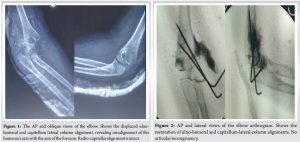

We preoperatively performed standard anteroposterior (AP) and lateral views of the elbow (Fig. 1). We performed a radiograph of the uninjured elbow for comparison. The differential diagnoses were transphyseal separation, lateral condyle humerus fracture, and elbow dislocation.

Under general anesthesia and in a supine position, closed reduction was done with longitudinal traction, mediolateral correction, and elbow flexion to stabilize the fracture. We did percutaneous pinning with two lateral 1.5 mm K-wires. We did arthrography by injecting Iohexol from the lateral aspect of the elbow. The arthrogram showed articular congruity (Fig. 2). Pins were bent, cut, left outside for easy removal, and immobilized at seventy degrees with a back slab. We did a post-operative CT to assess the fracture pattern and reduction. (Fig. 3).